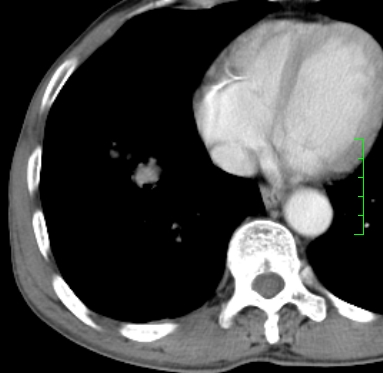

m,73y。膝关节疼痛伴双下肢水肿。入院常规胸片发现结节灶。增强为静脉期。

肿块周围可见局限性气肿,考虑肺癌可能性大。双肺上叶继发型肺结核。

指套征,强化明显,近侧肺组织局限性肺气肿,考虑支气管类癌,慢支、肺气肿、双上陈旧性tb、冠脉钙化。

1)考虑右肺下叶周围型肺癌。2)右肺上叶及左肺感染性病变(结核可能)。3)肺气肿。4)冠状动脉钙化。